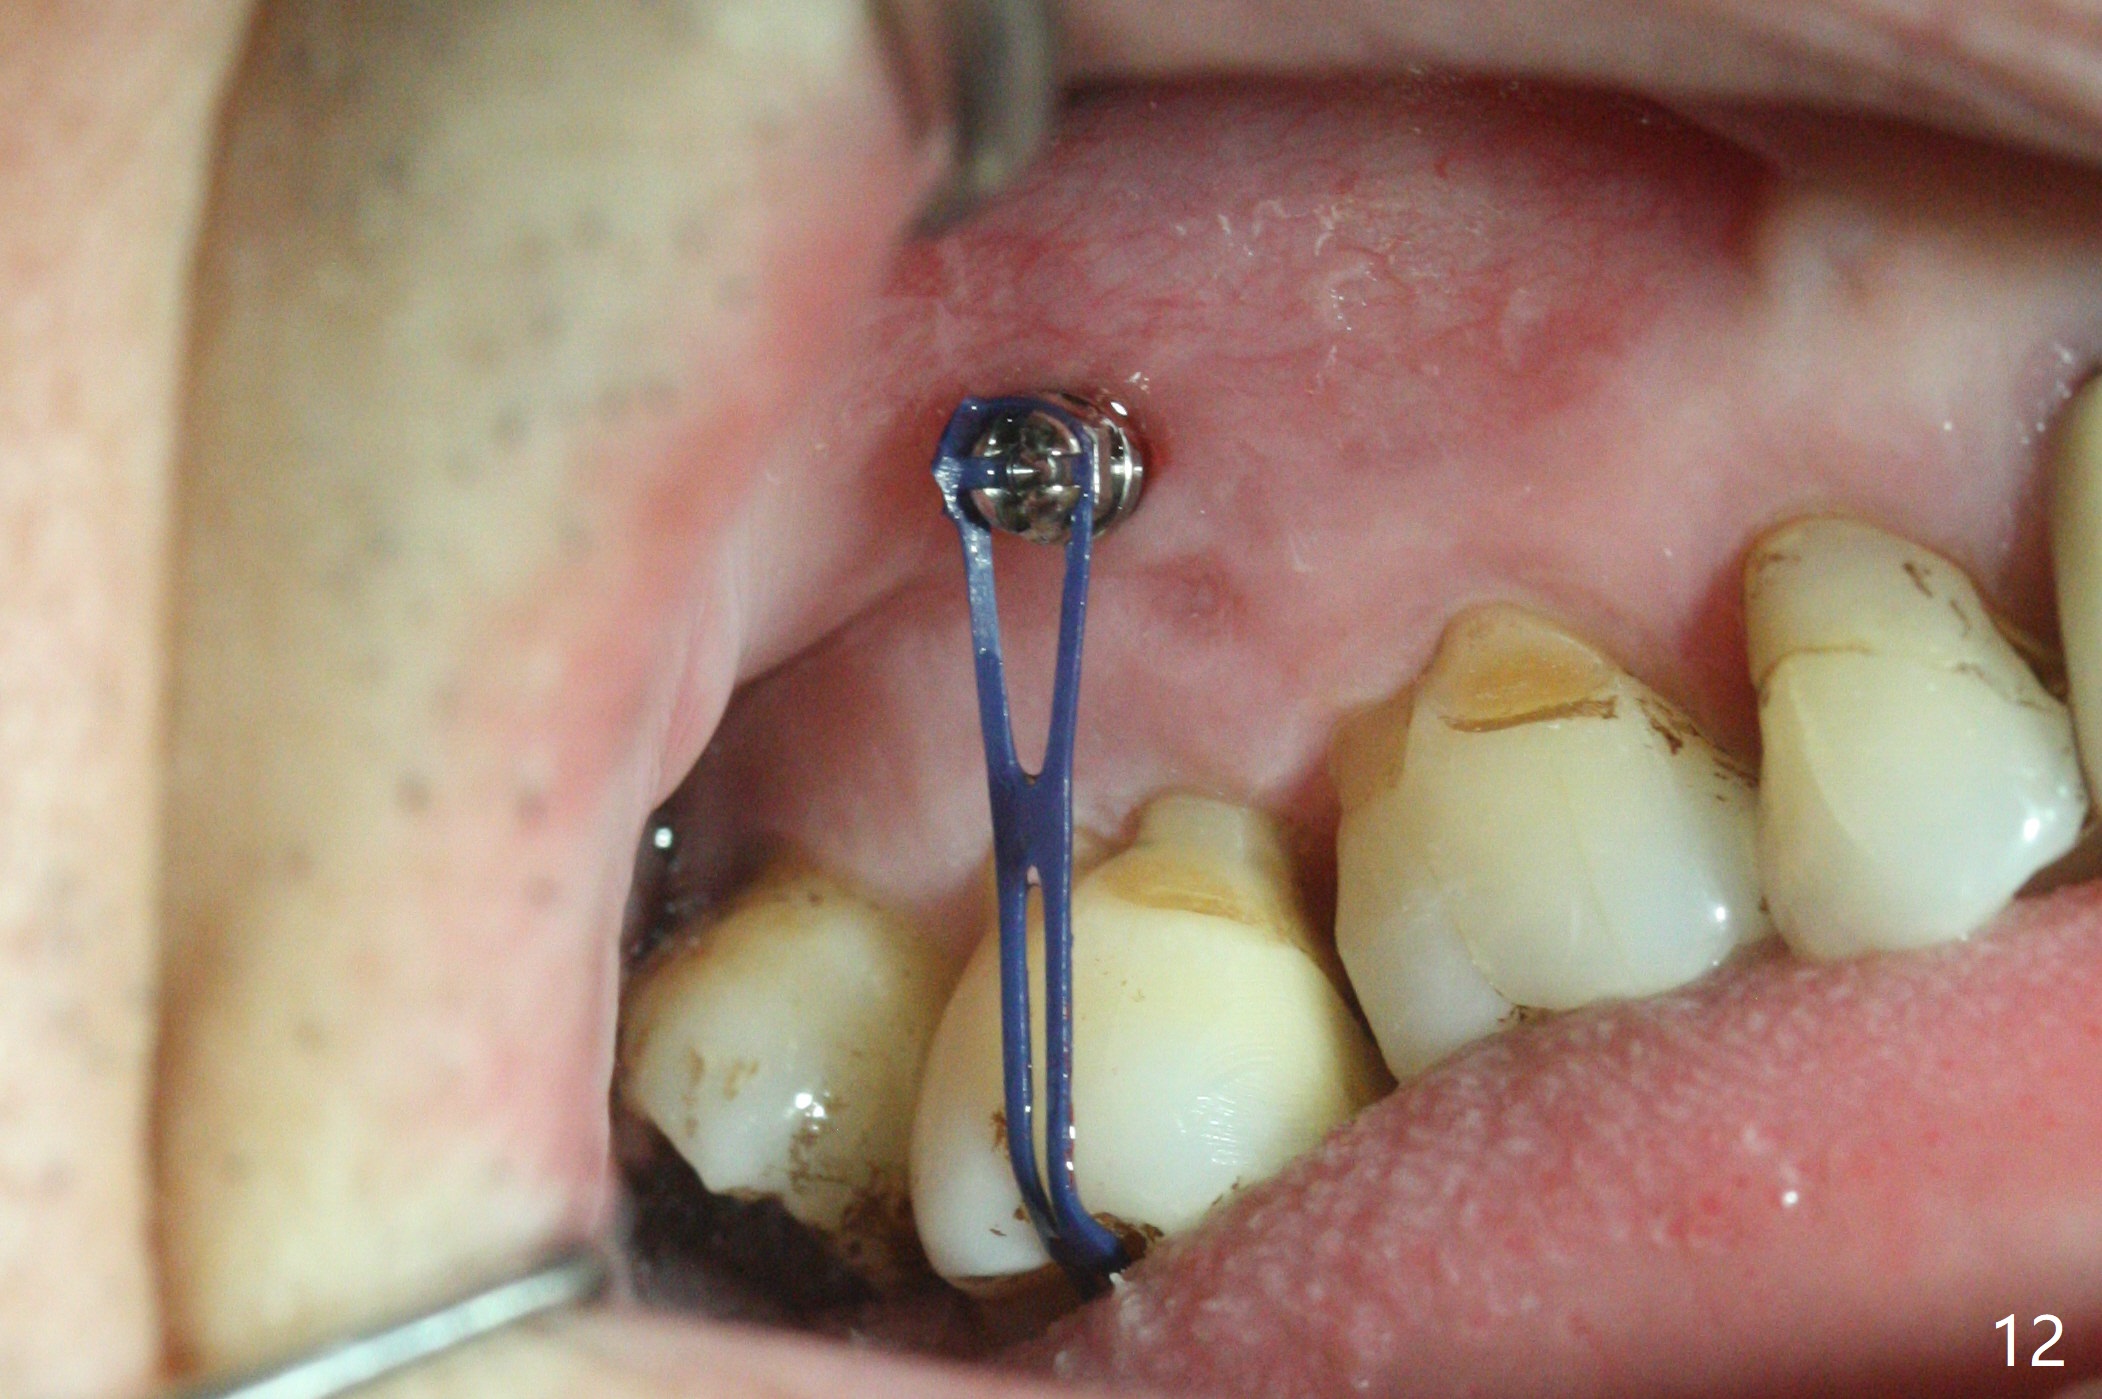

The buccal implant becomes loose in 2-3 months. When the wound heals (Fig.9 <), a 1.6x`10 mm implant is placed with the help of PAs for trajectory (Fig.10,11) and in the nonkeratinized gingiva (higher, the crestal bone may have been traumatized by previous implant placement, Fig.12). Two months later, the tooth #2 is partially intruded (Fig.13). A provisional (Fig.14 P) is fabricated in the osteointegrated implant at #31 with supraocclusion so that the remaining dentition has no occlusal contact (*). The periodontally compromised tooth #2 becomes in buccoversion in 2 months. The provisional is removed, while a lingual button is placed in the buccal surface of the tooth #2 (Fig.15). With power chain attached to the lingual mini-implant, the tooth #2 is lingualized in 2 months. The provisional and the implants are reused for final intrusion (Fig.16). The treatment is nearly 11 months. The buccal implant, although placed in the movable mucosa, remains stable and healthy (Fig.17). The tooth #1, as a guiding plane (to prevent #2 from distalization during intrusion), is not extracted after intrusion is completed.